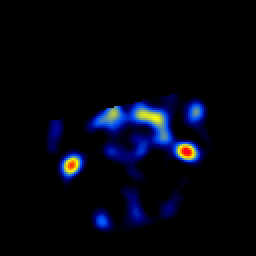

overlay -- Slice #5

[Home][Help][Clinical] Slice 5